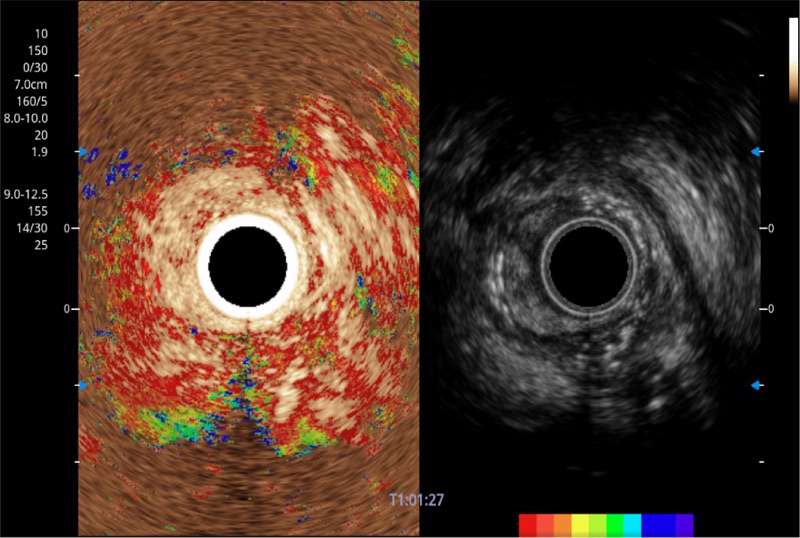

可人为将灰阶图像转变成彩色的显示方式,增强人眼对于不同回声强度的敏感度,主观上增加了图像分辨率

TIC时间强度分析曲线

具有四种造影成像效果